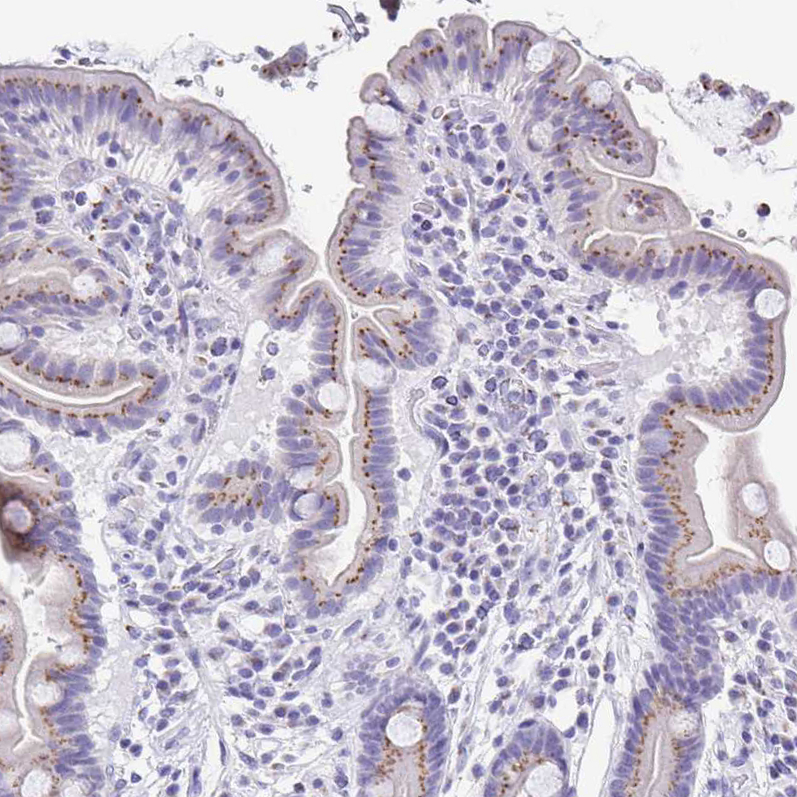

Immunohistochemistry analysis in human small intestine and pancreas tissues using HPA002107 antibody. Corresponding SULT1B1 RNA-seq data are presented for the same tissues.